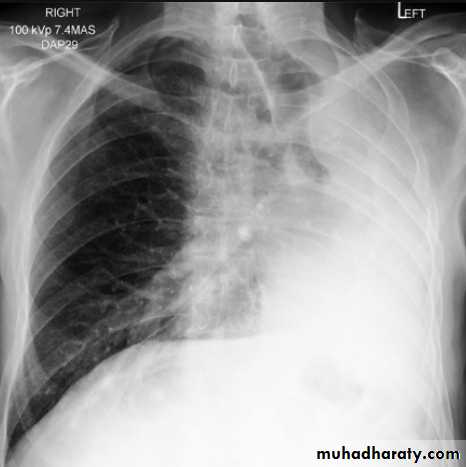

Right middle lobe collapse has distinctive features, and is usually relatively easily identified.

Radiographic features

Chest radiograph

Frontal chest XR showing opasity cause obscuration of the RT cardiac border

Lateral chest XR film the opacity is tongue like shape

versus (triangular in shape) in RT middle lobe consolidation seen in lateral chest XR film

RT lower lobe collapse

usually the medial aspect of the dome of right hemidiaphragm is lost.

the right hilum is depressed

It is important to note that the right heart border, which is contacted by the right middle lobe remains well seen.

Non-specific signs indicating right sided atelectasis may also be present (although due to the small size of the right middle lobe they may well be subtle). They include:

elevation of the hemidiaphragm

crowding of the right sided ribs

shift of the mediastinum to the right